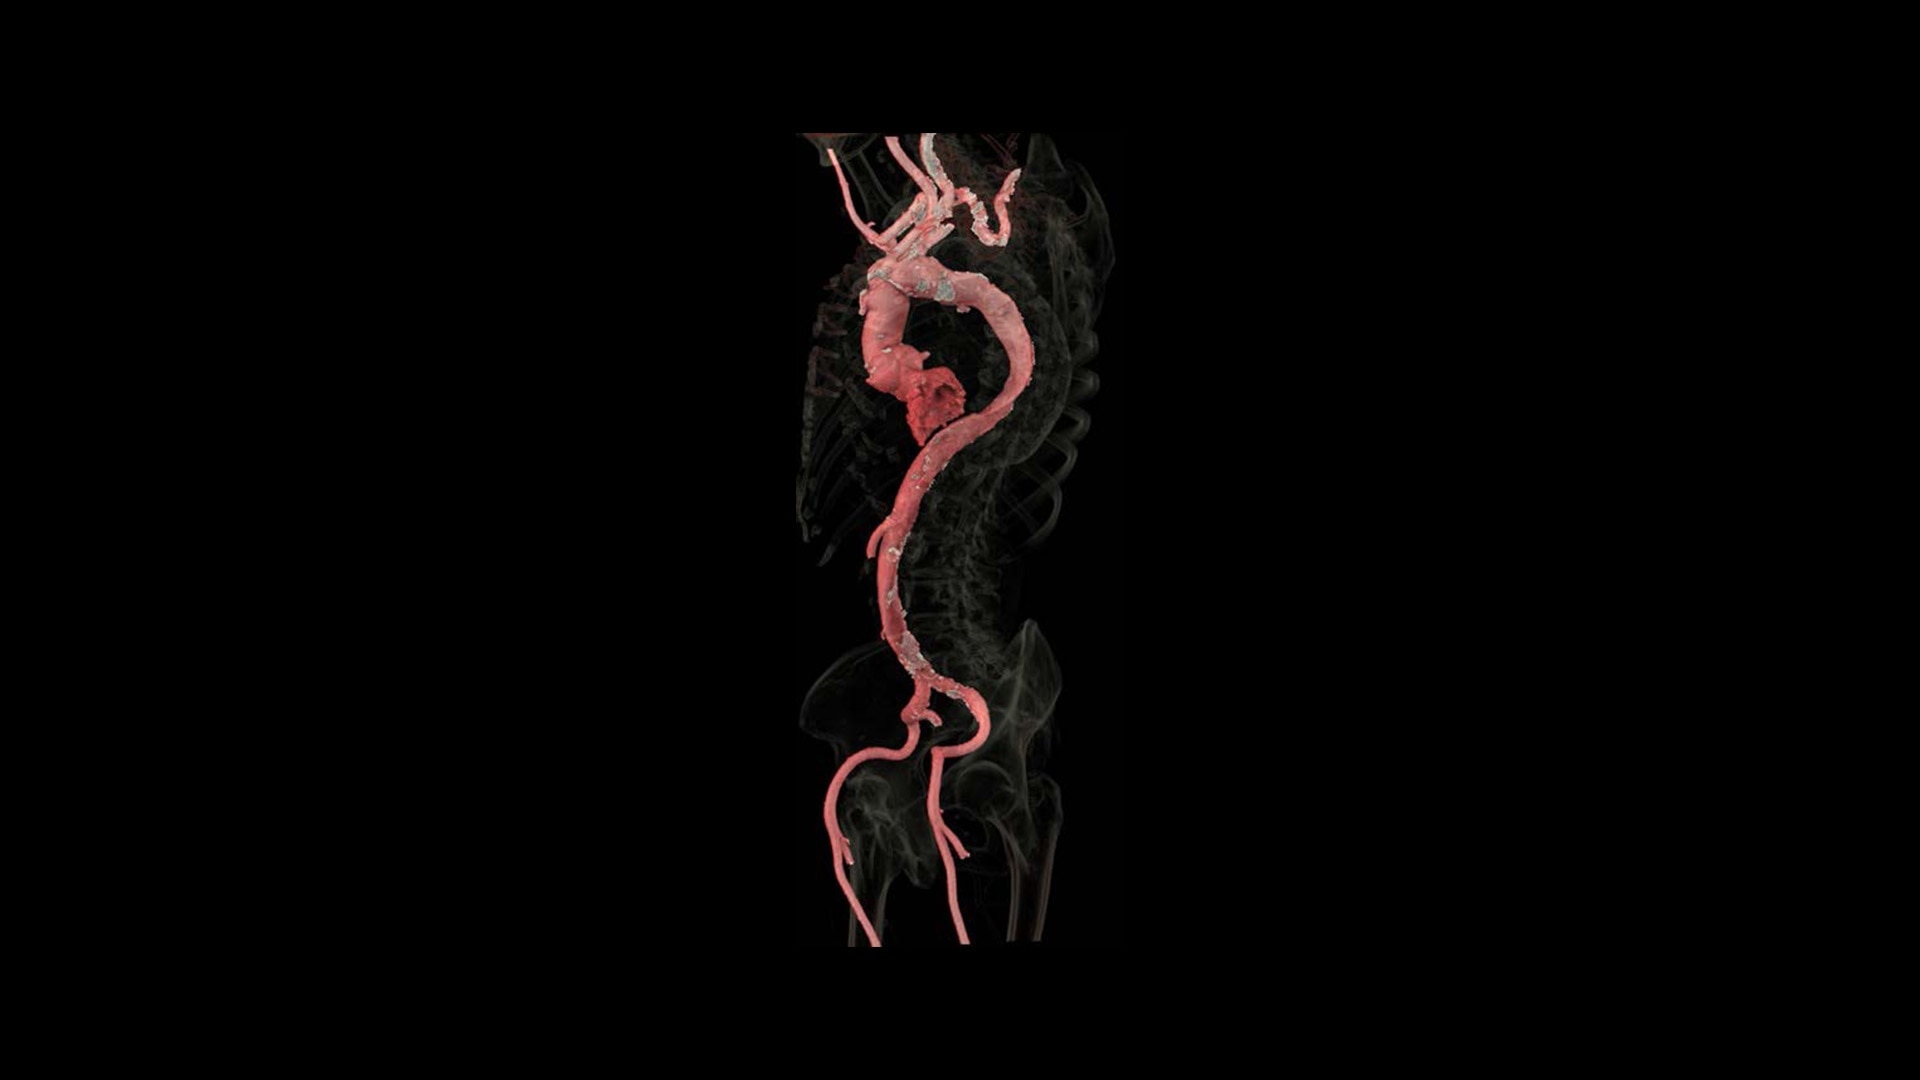

Introducing the new Revolution™ Ascend Platform, our latest CT offering designed to efficiently match your imaging demands. Whether you require a highly efficient system with 20 mm of coverage for routine scanning or a more advanced system with 40 mm of coverage that improves low contrast detectability, you can choose exactly what you need. Since the Revolution Ascend Platform is scalable, you can invest in the CT you need today and take comfort in knowing that it’s ready for tomorrow.

The Revolution Ascend Platform is ready for your CT department's clinical needs and efficiency demands. By offering advanced clinical capabilities, exceptionally efficient workflow as well as the latest in scalable imaging technology, you will have a CT that can keep you ahead of today's patients and tomorrow's challenges.

You’ll be ready for what’s next

The Revolution Ascend Platform’s scalable and upgradeable design lets you invest in the clinical capabilities you need today, while enabling your CT to grow with you in the future. The Revolution Ascend Select can be upgraded to Plus or Elite. And Plus can be upgraded to Elite. All of the configurations are paired with Effortless Workflow and Smart Subscription for the most efficient CT experience.